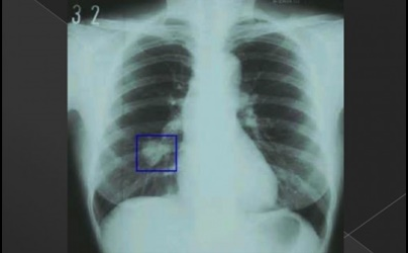

혈전은 반드시 폐암이 아니어도 나타날 수 있습니다 . 혈담이란 기침 후에 피가 나오 거나 가래에 피가 섞여 있는 것을 혈담 이라고 합니다 . 그러나, 의심스러운 폐암의 초기 증상의 혈담은, 선홍색의 비교적 선명한 피가 나오는 것을 의심해 봐야 합니다 . 이것은 암세포 때문에 폐가 괴사하기 때문 입니다 . 이 경우 폐암 초기보다는 암세포가 확장되었다고 보는 것이 좋습니다 . 폐암 환자의 25% 가 혈담을 했다고 통계가 나온 적이 있습니다 .

6. 폐암 초기 증상 - 혈담